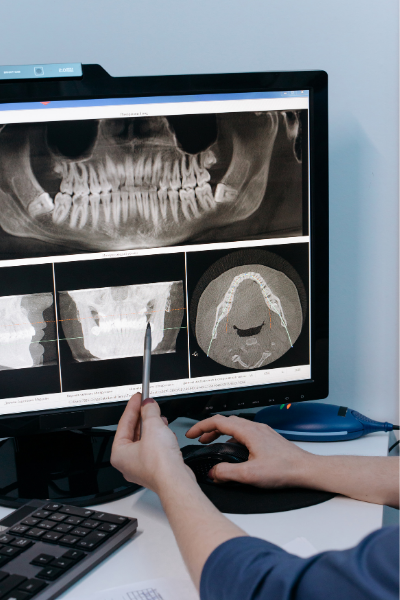

Os técnicos de radiologia são profissionais de saúde que efetuam exames na área da radiologia, ou seja, atuam na produção de imagens do interior do corpo que permitem diagnosticar situações patológicas como pneumonias, tumores ou fraturas ósseas, entre outras. As suas principais funções consistem na programação, execução e avaliação de todas as técnicas radiológicas utilizadas no diagnóstico, na prevenção e promoção da saúde, recorrendo, para esse efeito, a equipamentos tecnologicamente avançados.

Para as radiografias extra orais:

Já nas radiografias extra orais deve- se utilizar:

• Deve utilizar o menor campo ou igual do tamanho do filme;

• O operador deve observar o paciente durante todo o procedimento.